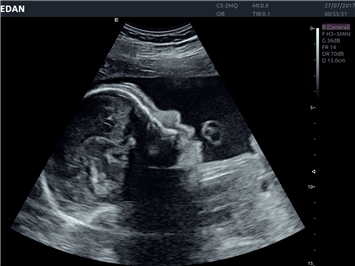

• Акушерства и гинекологии

• Автоматизированные измерения в акушерстве